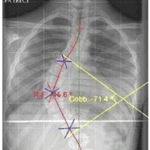

- A pelvic obliquity caused by sacral deformity or leg length discrepancy can mask a lumbar scoliosis. These figures were primarily used in large-scale adolescent screenings, such as in school settings, to minimize unnecessary X-rays. However, in one-on-one scenarios with patients, where a more comprehensive assessment is possible, it is easier to identify individuals who require referral. A diagnosis of scoliosis is confirmed when a patient has a Cobb angle of 10 degrees or more on X-ray, accompanied by rotation (Figure 4). AIS is diagnosed when the patient is between 10 and 18 years old, and no known cause for the scoliosis has been identified (7).